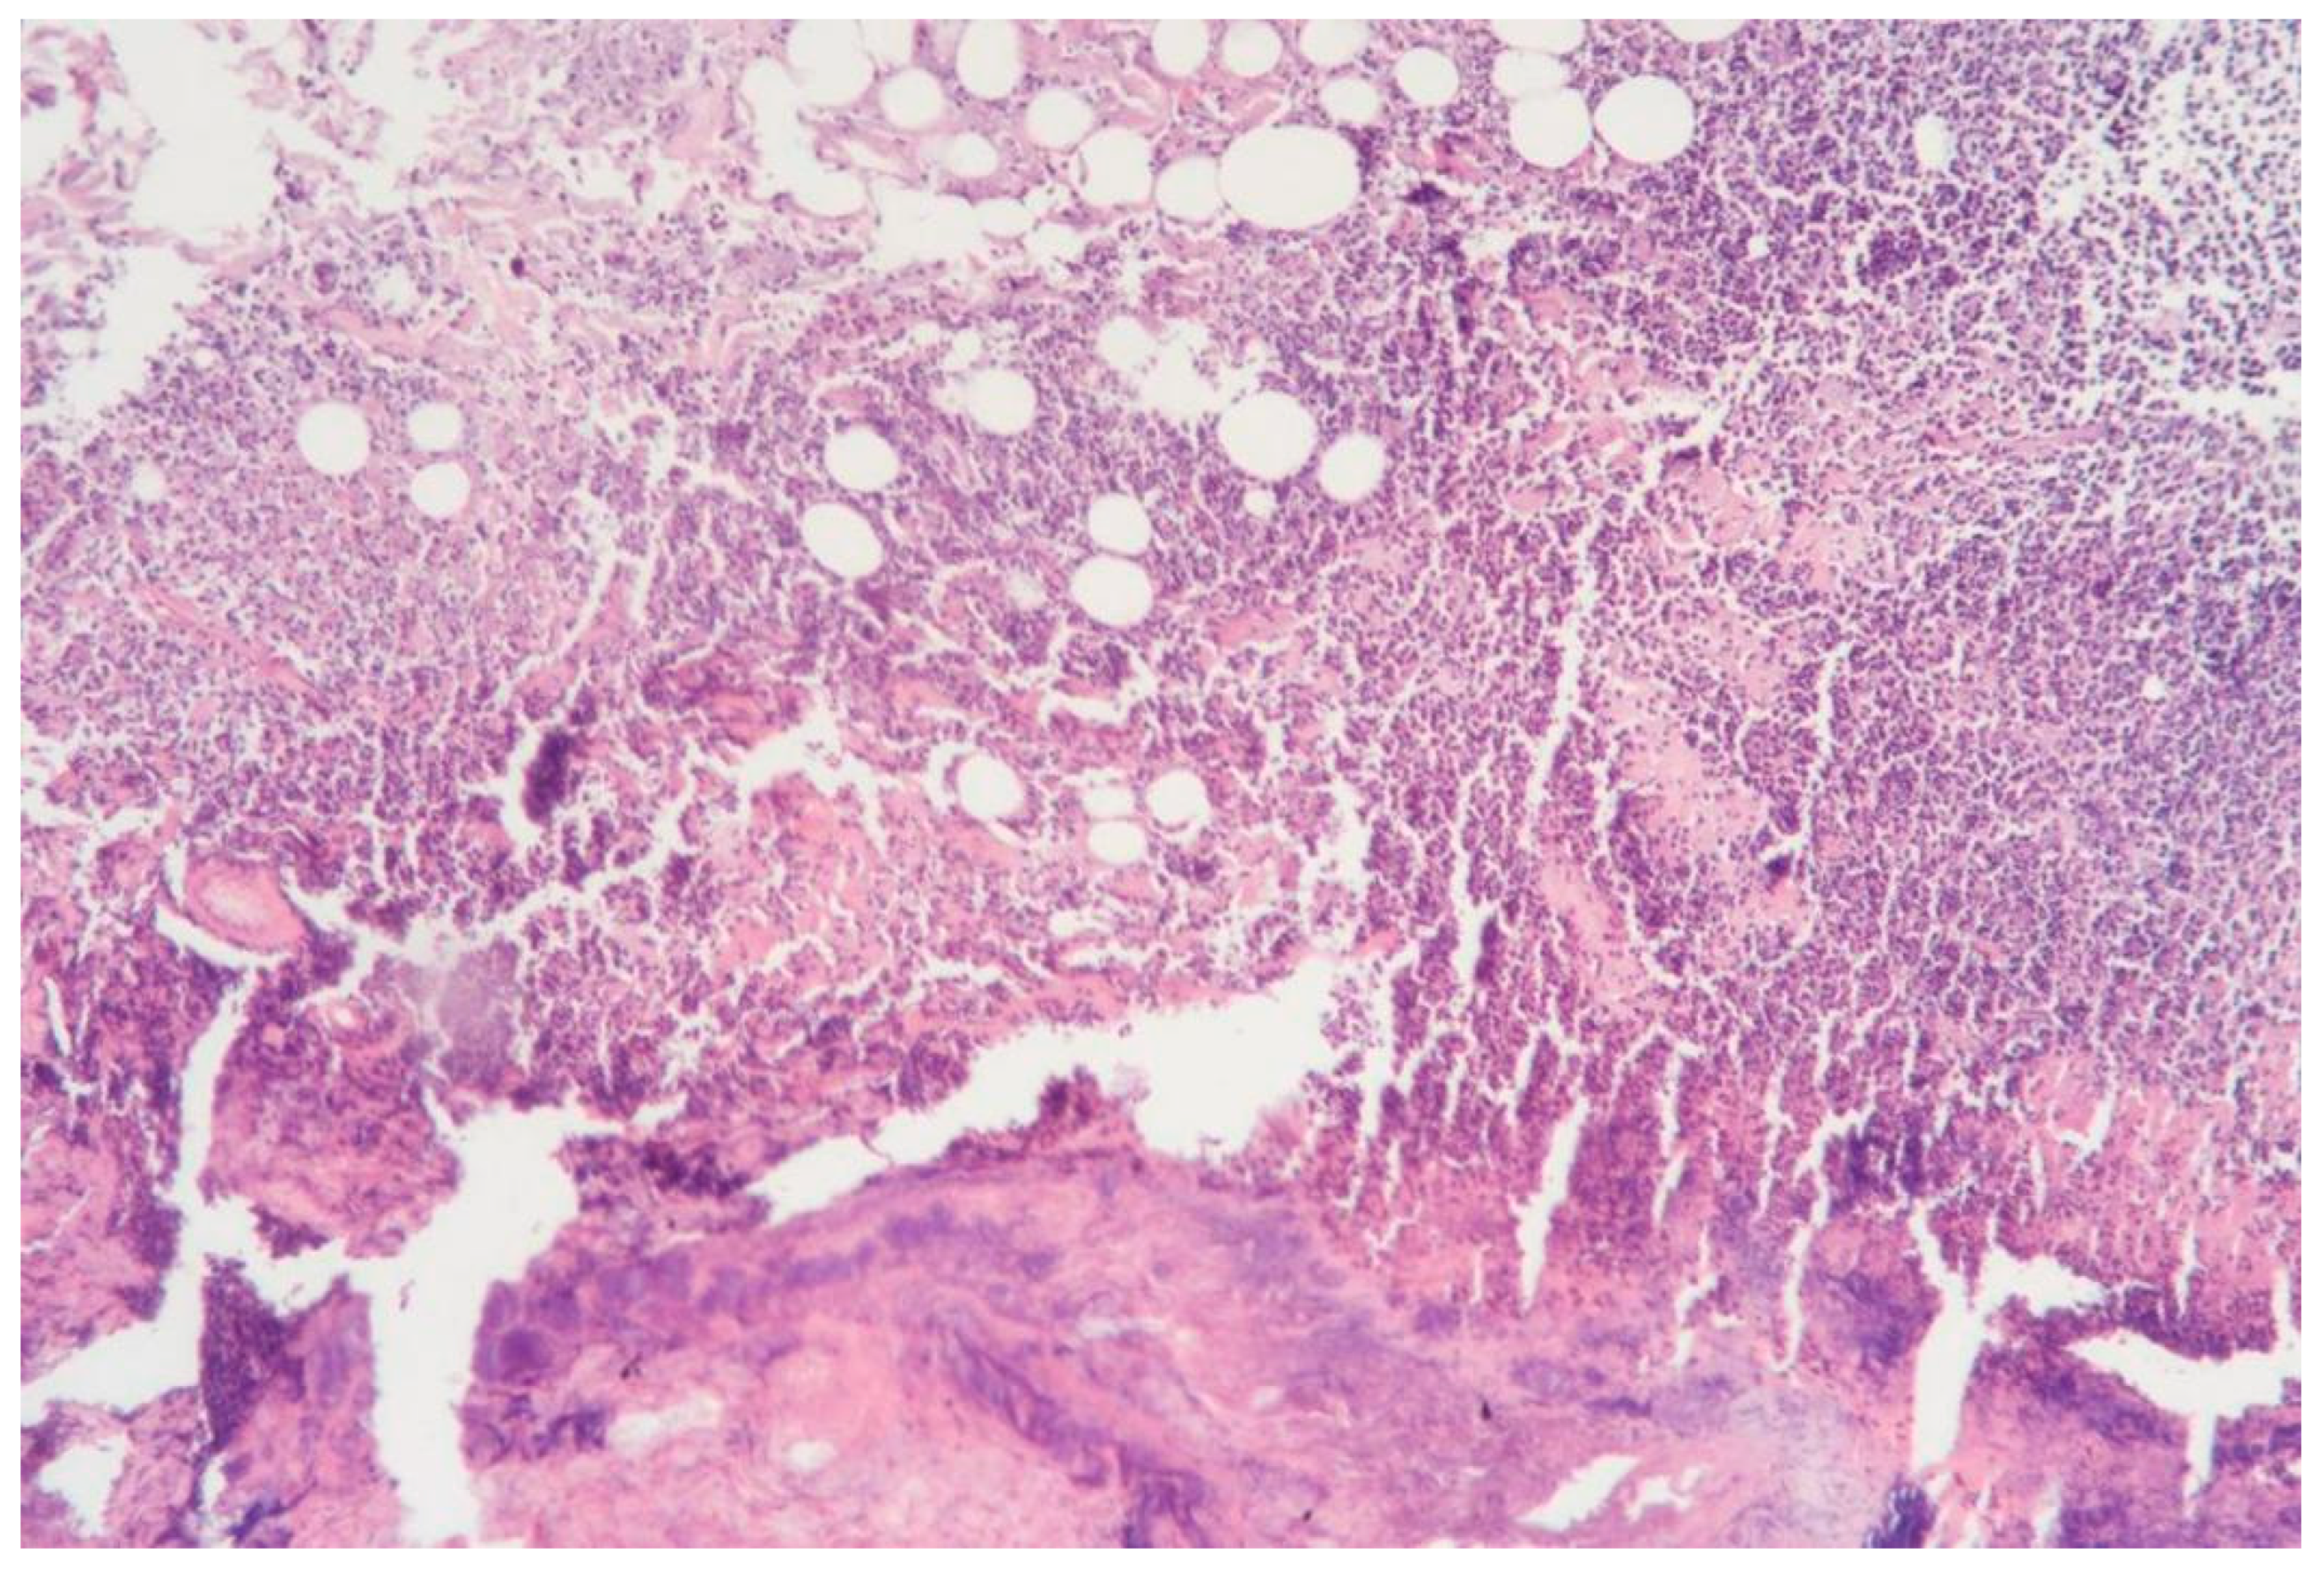

3.1.8. Clinical Case 8: Adipose Tissue Dissection Area, 15 W (See Figure 9)

Description: The coagulative necrosis of the adipose tissue was primarily along the septa. The vessels in the subcutaneous adipose tissue were congested; small-caliber vessels were coagulated, while larger vessels showed necrosis of the perivascular space, polarization, and sloughing of endothelial cells. Inflammatory changes were absent.

Figure 9. Changes in subcutaneous adipose tissue following exposure to the thulium laser at 15 W 75 Hz. H&E staining, 10× objective magnification.

3.1.9. Clinical Case 9: Adipose Tissue Dissection Area, 20 W (See Figure 10)

Description: Compared to 15 W, the zone of coagulative necrosis was less pronounced.

Figure 10. Changes in subcutaneous adipose tissue following exposure to the thulium laser at 20 W, 100 Hz. H&E staining, 10× objective magnification.

Thus, when exposed to the thulium laser at 20 W, the surrounding tissues exhibited the least pronounced necrotic changes, with no hemorrhages or inflammatory alterations.